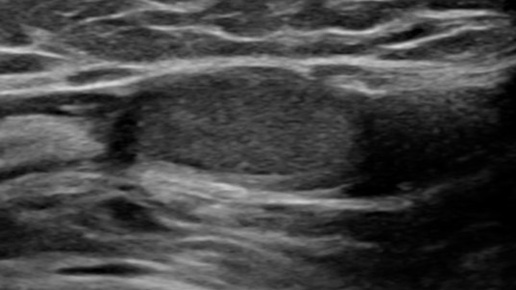

Ложный крипторхизм (УЗИ)